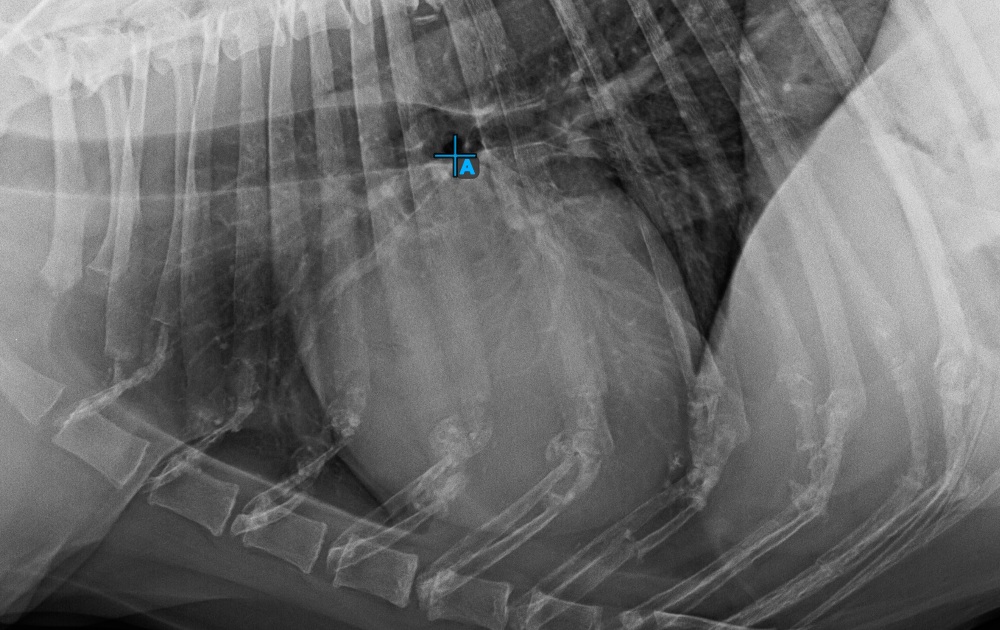

Start the measurement by marking the Bifurcatio tracheae, near the top of the heart.

The image below represents a typical placement of the Bifurcatio tracheae point.